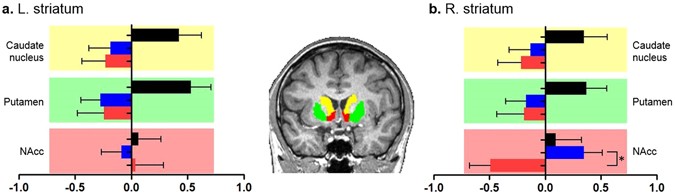

Table 2 and Figure 2 represent the striatal volumes obtained from FreeSurfer. The estimated total intracranial volume (eTIV) was different among the three groups (P = 0.013) but not between the Internet gaming user groups (P = 0.430). Although the volumes of the bilateral caudate nucleus and putamen were not significantly different among three groups (Table 2; left caudate nucleus, P = 0.795; left putamen, P = 0.126; right caudate nucleus, P = 0.987; right putamen, P = 0.833), Figure 2 illustrates a distinct difference between the Internet gaming groups and NGC group by presenting the results of the comparisons of the standardized striatal volumes. The Internet gaming groups showed negative values in the volumes of the bilateral dorsal striatum, consisting of the caudate nucleus and putamen, compared with the NGC group that showed positive values. We found that the volume of the right NAcc, adjusting for age and eTIV, was significantly different among the three groups, and this difference still survived a more stringent correction for multiple comparisons. A post hoc analysis revealed that this volumetric difference was driven by the smaller volume in the IGD group than that in the IGC group.

Comparisons of the standardized striatal volumes among the Internet gaming disorder (IGD), Internet gaming control (IGC), and non-gaming control (NGC) groups. (a,b) Although the volumes of the bilateral caudate nucleus and putamen were not significantly different among three groups, (b) the volume in the right nucleus accumbens (NAcc) was different, which was driven by the smaller volume in the IGD group than that in the IGC group, adjusting for age and the estimated total intracranial volume (eTIV). In the brain image, each color represents a brain region (yellow: the caudate nucleus, green: putamen, red: nucleus accumbens). The colors of the bar graphs indicate the following: black, NGC group; blue, IGC group; red, IGD group. The outputs of the striatal areas, which were obtained from FreeSurfer, are overlaid on the brain image of a subject. *Significant at P < 0.05.